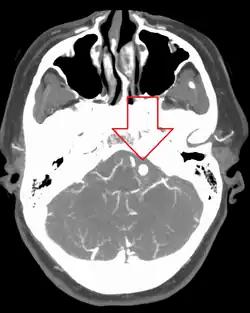

![]() | |

| Angiography of an aneurysm in a brain artery. The aneurysm is the large bulge in the center of the image. | |

Diagnosis of a ruptured cerebral aneurysm is commonly made by finding signs of subarachnoid hemorrhage on a computed tomography (CT) scan. If the CT scan is negative but a ruptured aneurysm is still suspected based on clinical findings, a lumbar puncture can be performed to detect blood in the cerebrospinal fluid. Computed tomography angiography (CTA) is an alternative to traditional angiography and can be performed without the need for arterial catheterization. This test combines a regular CT scan with a contrast dye injected into a vein. Once the dye is injected into a vein, it travels to the cerebral arteries, and images are created using a CT scan. These images show exactly how blood flows into the brain arteries.[39]